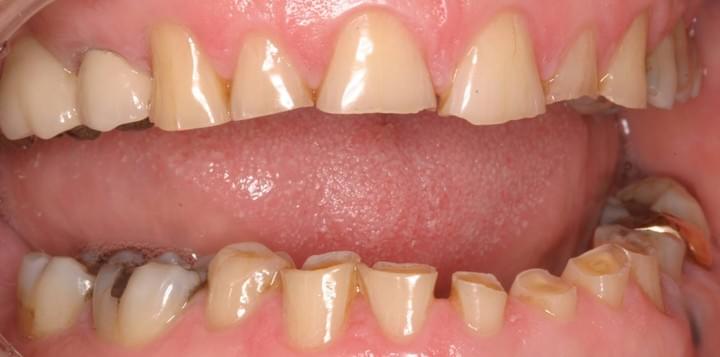

- Sensitive Teeth - Sensitive teeth can impact your eating experience. It is important to determine its exact nature and receive treatment as soon as possible.  - Gum recession - Gum recession is mainly caused by periodontal disease, aggressive brushing and/or use of abrasive products. When gums recede, roots will be exposed and they can be very sensitive to temperature and pressure. Continuous hard brushing can exaggerate the sensitivity and makes it harder to be managed conservatively.  - Tooth decay - Tooth decay exposes inner structure (dentine). When bacteria gets closer to the nerve tissues, hot/cold things can be directly conducted and amplify the sensations, thus causing sensitive teeth.  - Grinding/clenching (bruxism) - Grinding your teeth can wear them down and even cause the teeth to flex along the gum line (abfraction). Continuous grinding habit can cause many dental complications on the long term.  - Dental erosion/erosive wear - Dental erosion is usually caused by an acidic diet (alcohol, soft drinks and citrus) and gastroesophageal reflux disease (GERD). Since the acid will corrode the teeth, inner structure (dentine) will be exposed and cause dentinal hypersensitivity. Placing fillings on erosive wear can be difficult and they tend to last shorter.

- Brushing Abrasion - When you brush with the wrong technqiue, an unsuitable toothbrush and use abrasive oral products, brushing abrasion/abrasive wear can happena and progress irreversibly. - Most common treatment options: - Cause(s) and relevant risk factors must be identified

- Consequences 1: Gum recession, exposed roots and tooth sensitivity - Gum recession can happen with abrasive wear. When gums recede, roots of the teeth are exposed and they can be very sensitive to temperature and pressure. Continuous hard brushing can exaggerate the sensitivity and makes it harder to be managed conservatively.  - Consequences 2: Tooth decay and crown fracture - When more roots wear away with ongoing hard brushing, notches on roots along the gum line become deeper and bigger. Brushing can become difficult and the risk of tooth decay increases. Besides, the strength of the tooth along the notches becomes weaker, and abfraction can happen. The crown can potentially break and tooth removal may be required.  - Consequences 3: Aesthetics - With exposed roots and the present of abrasive wear, your appearance can be compromised because of their shapes and a more yellowish colour. They can be challenging to manage with conservative treatment and other restorative options can be expensive and difficult.